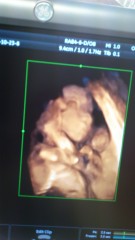

動き回って動き回ってなかなか顔を見せてくれませんでしたが、先生も長い時間粘ってくれてようやく見れた写真です。今日性別も分かり男の子でした!